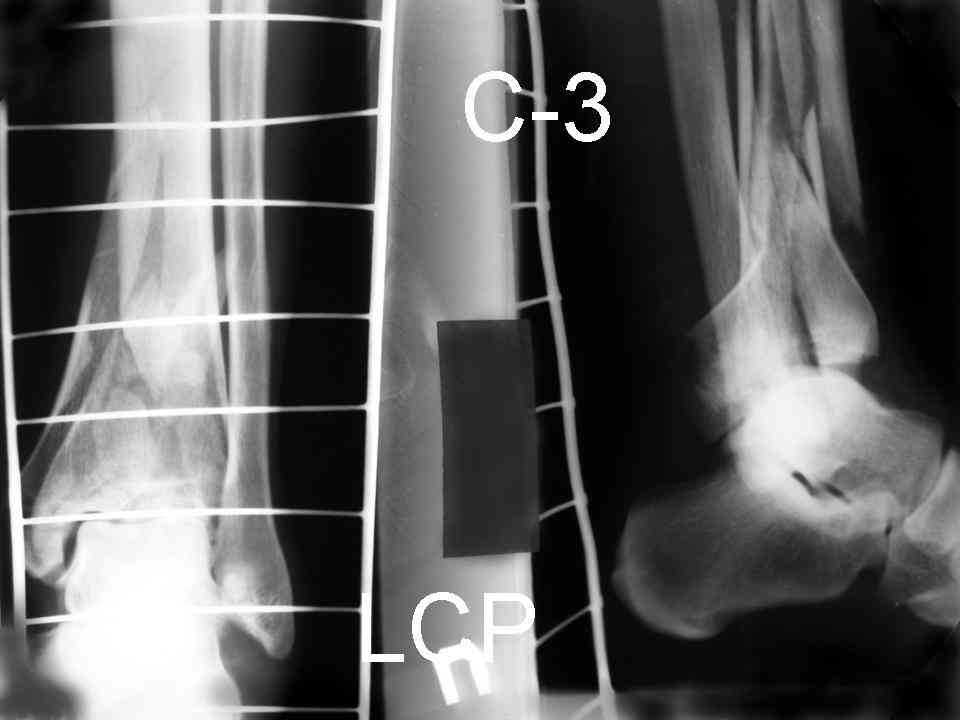

На рентгенограммах типичный перелом пилона по типу С-3. есть опыт до 100 открытых опреаций у нас в клинике. 20 примерно в год. Принцип один -все внутрисуставные переломы нуждаются в открытой репозиции и внутренней стабильной фиксации. При поступлении КТ не надо, так как получается только нагромождение костей. Истинной картины нет. Главное восстановить длину малоберцовой кости - это ключ к успеху. При поступлении меньше всего надо думать о сосудистых расстройствах, т.к. сама операция и репозиция даже сначала частичная даёт улучшение сосудитых нарушений. Причём очень быстро. Операция в 2этапа. При поступлении доступ позади наружной лодыжки, причём обязательно. После этого репозиция малоберцовой кости и фиксация пластиной 1/3 трубки под винт 3,5. Дренаж и любой аппарат наружной фиксации. Затем после спадения отёка на 5-7-10 день аппрат снимается и дугообразный разрез спереди от медиальной лодыжки 10-12 см. Главной чтобы расстояние между 1 и вторым разрезом было не меньше 7-8 см. Тогда не будет некрозов лоскутов. Таранная кость используется как матрица на неё укладываются отломки и фиксируются пицами. Ренг-контроль. Отломки лежат все отдельно, но ничего не высыпется. При переломах С-3 всегда нужна костная пластика (из крыла). Фиксация пластиной лист клевера простой или LCP. Гипс не нужен. Дренаж до 48 часов. Операция длится 3-4 часа обязательно без жгута. Посылаю примерно такой же случай.

Ещё есть одна проблема когда есть перелом малоберцовой кость, то всё ясно. А когда малоберцовая кость не повреждена, то сразу накладывается аппрат наружной фиксации при поступлении, чтобы как бы перерастянуть отломки и главное убрать вальгусное или варусное смещение, а потом на 5-7 день открыто большеберцовая кость восстанавливается и фиксируется пластиной. С уважением Дрягин